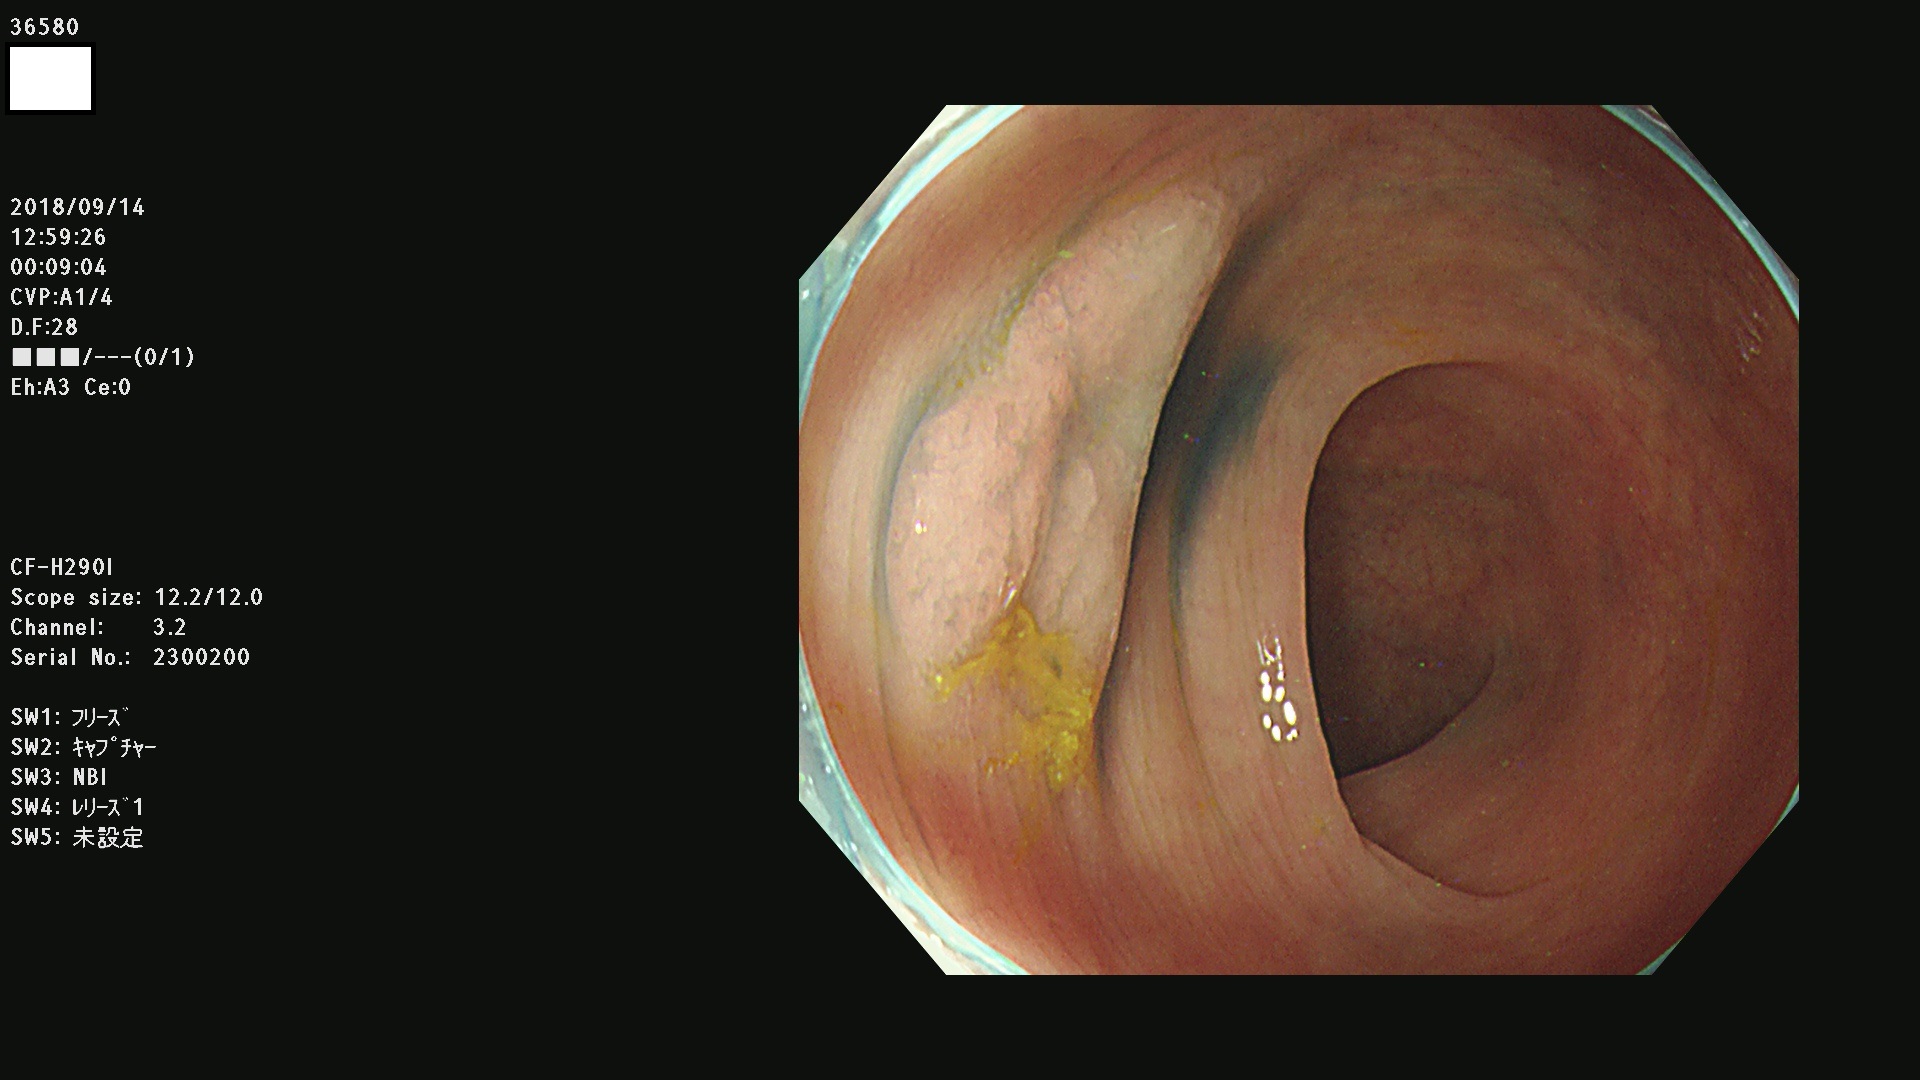

36500 36503 36504 36505 36507(SSAPのみ) 36508 36509 36510 36511 36514 36515 36517 36518 36520 36522(SSAPのみ) 36523 36524 36526 36528 36530 36531 36532 36533 36534 36535 36536 36538 36541 36542 36543 36544 36545 36546 36548 36550 36551 36554 36555 36556 36558 36559 36560 36561 36564 36565 36567 36568 36570 36572 36573 36574 36575 36576 36577 36578 36579 36580 36582 36584 36586 36591 36592 36593 36594 36595 36596 36597 36598

発見困難で危険性の高い平坦型病変(上記100名より抽出)